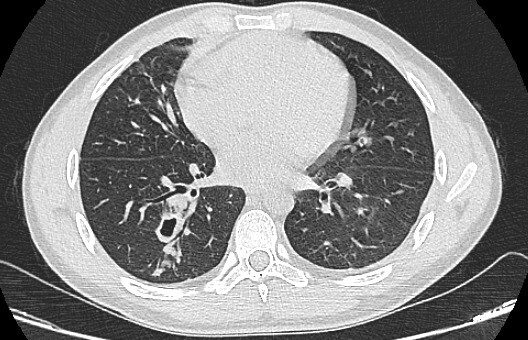

Hình ảnh phim chụp cắt lớp phổi của bệnh nhân sán lá phổi. Ảnh BVCC.

Tại Bệnh viện Đa khoa Đức Giang, sau khi thăm khám và làm các xét nghiệm, các bác sĩ phát hiện bệnh nhân nhiễm sán lá phổi.